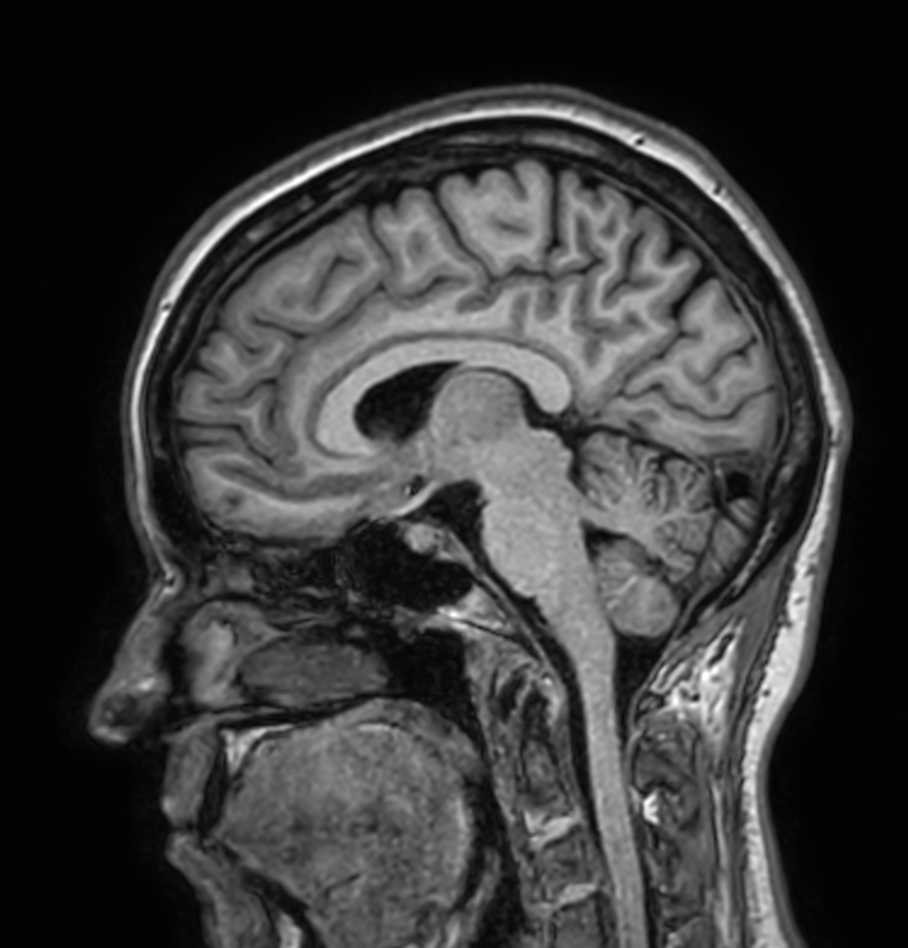

Sagittal 3D T1w TFE